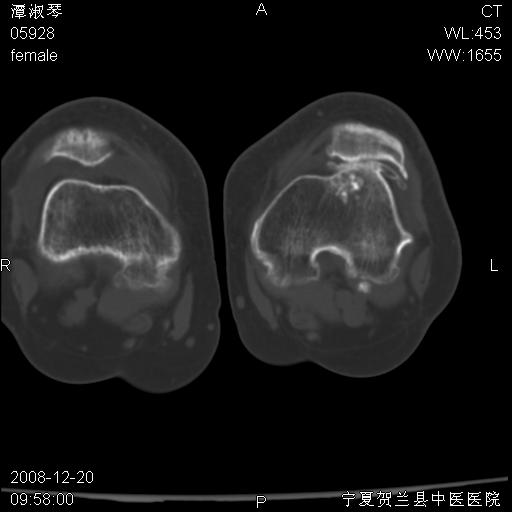

标题: CT17526:请各位看看是啥?

支持骨梗死,退行性骨关节病,膝关节积液.

考虑骨梗死可能性大

骨梗死可能性大

左股骨下段骨梗死。双膝退变。

左胫骨下端松质骨及髓腔内可见点片状高密度灶,骨皮质无明显膨胀及变薄。病变范围较长。支持骨梗死,退行性骨关节病,膝关节积液